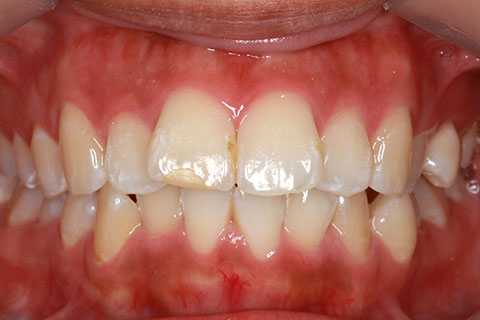

ハーフリンガル矯正3:上の歯のみ舌側矯正で治療(矯正期間24ヶ月)

治療前

治療中(開始直後)

治療中(開始半年後)

治療後

- 年齢・性別

- 25歳女性

- 治療期間

- 2年0ヶ月

- 抜歯

- 上下4番抜歯

- 治療費

- 110万円

- 治療内容

- 表側矯正と比較して、力学的な操作性が複雑なため、ボーイングエフェクトを起こしやすい。